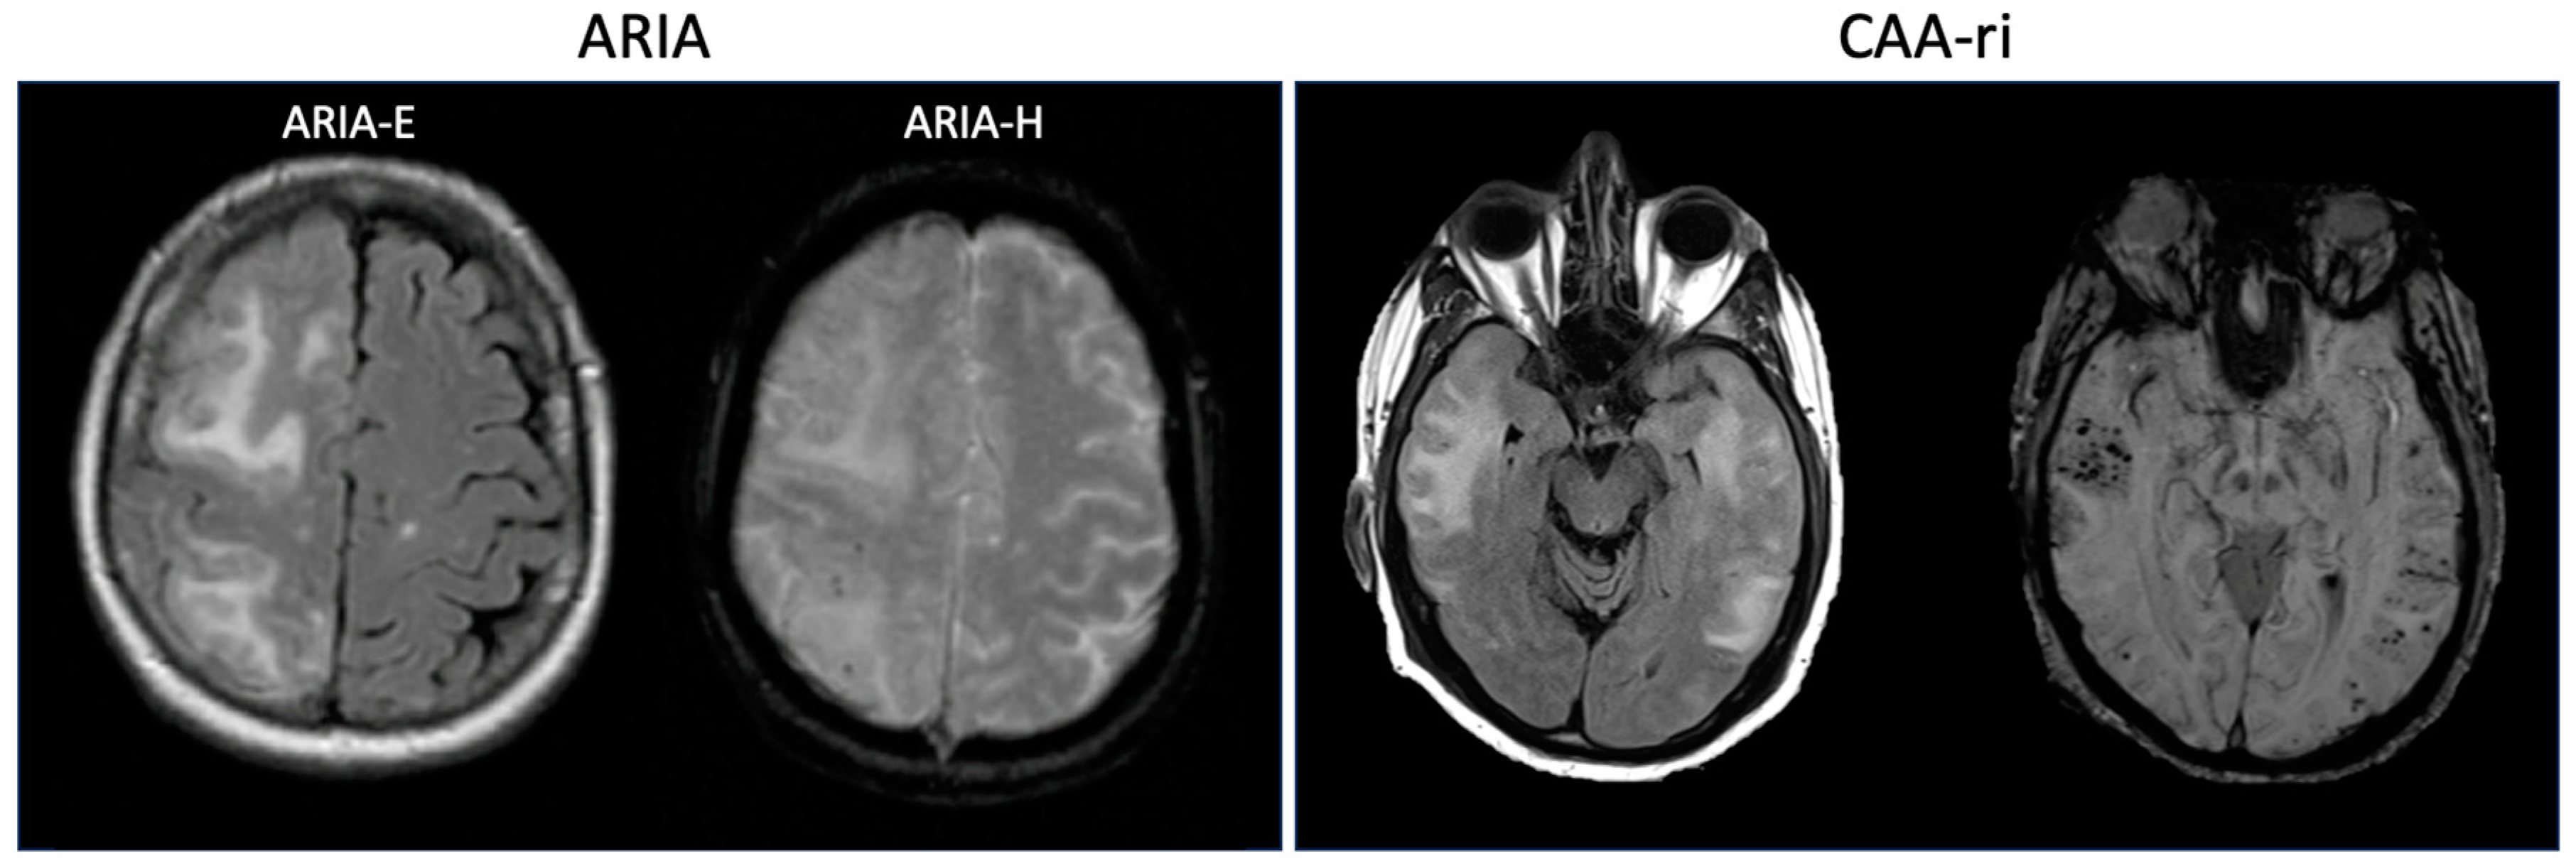

| Mild | Moderate | Severe | Location of Increased Vascular Permeability | ||

|---|---|---|---|---|---|

| Parenchyma | Leptomeninges | ||||

| ARIA-E | FLAIR hyperintensity confined to sulcus and or cortex/subcortical white matter in one location < 5 cm | FLAIR hyperintensity 5 to 10 cm, or more than 1 site of involvement, each measuring <10 cm | FLAIR hyperintensity measuring >10 cm, often with significant subcortical white matter/sulcal involvement. May involve one or more separate sites | “Vasogenic edema” | Sulcal effusion/exudate |

| ARIA-H | ≤4 new microhemorrhages on T2*-GRE OR 1 focal area of superficial siderosis on T2*-GRE | 5 to 9 new microhemorrhages OR 2 focal areas of superficial siderosis | 10 or more new microhemorrhages OR >2 focal areas of superficial siderosis | Microhemorrhages | Superficial hemosiderosis |